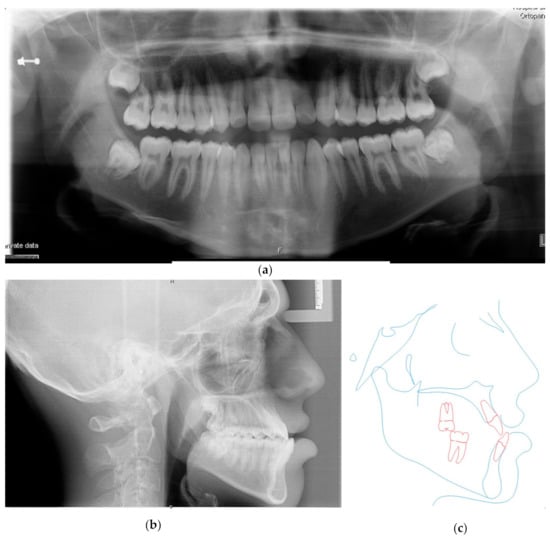

3.3. Postsurgical Orthodontic Treatment

3.4. Treatment Results